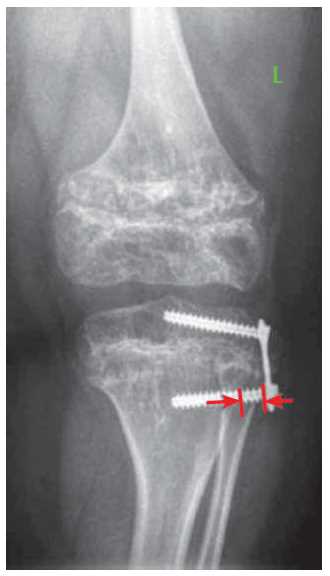

Incomplete adjoining was considered as the distance between the plate and the bone surface of more than 2 mm. Measurements were made from the base of the cap of the screw to the edge of the cortical plate of the metaphyseal part of the bone (Fig. 2).

Fig. 2. X-ray of the left knee in a direct projection of the patient T., 10 years old. Diagnosis: "Spondyloepiphisal dysplasia. Varus deformation of the lower extremities "(the arrows indicate the zone of incomplete abutment of the plate)